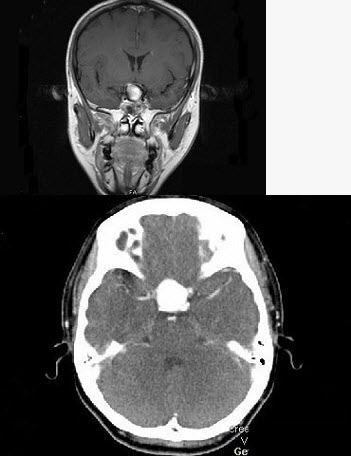

女,43岁,反复头痛10个月,CT检查如图,最可能诊断为()。

A、颅咽管瘤

B、垂体瘤

C、颈内动脉瘤

D、脑膜瘤

E、胶质瘤

正确答案:

C